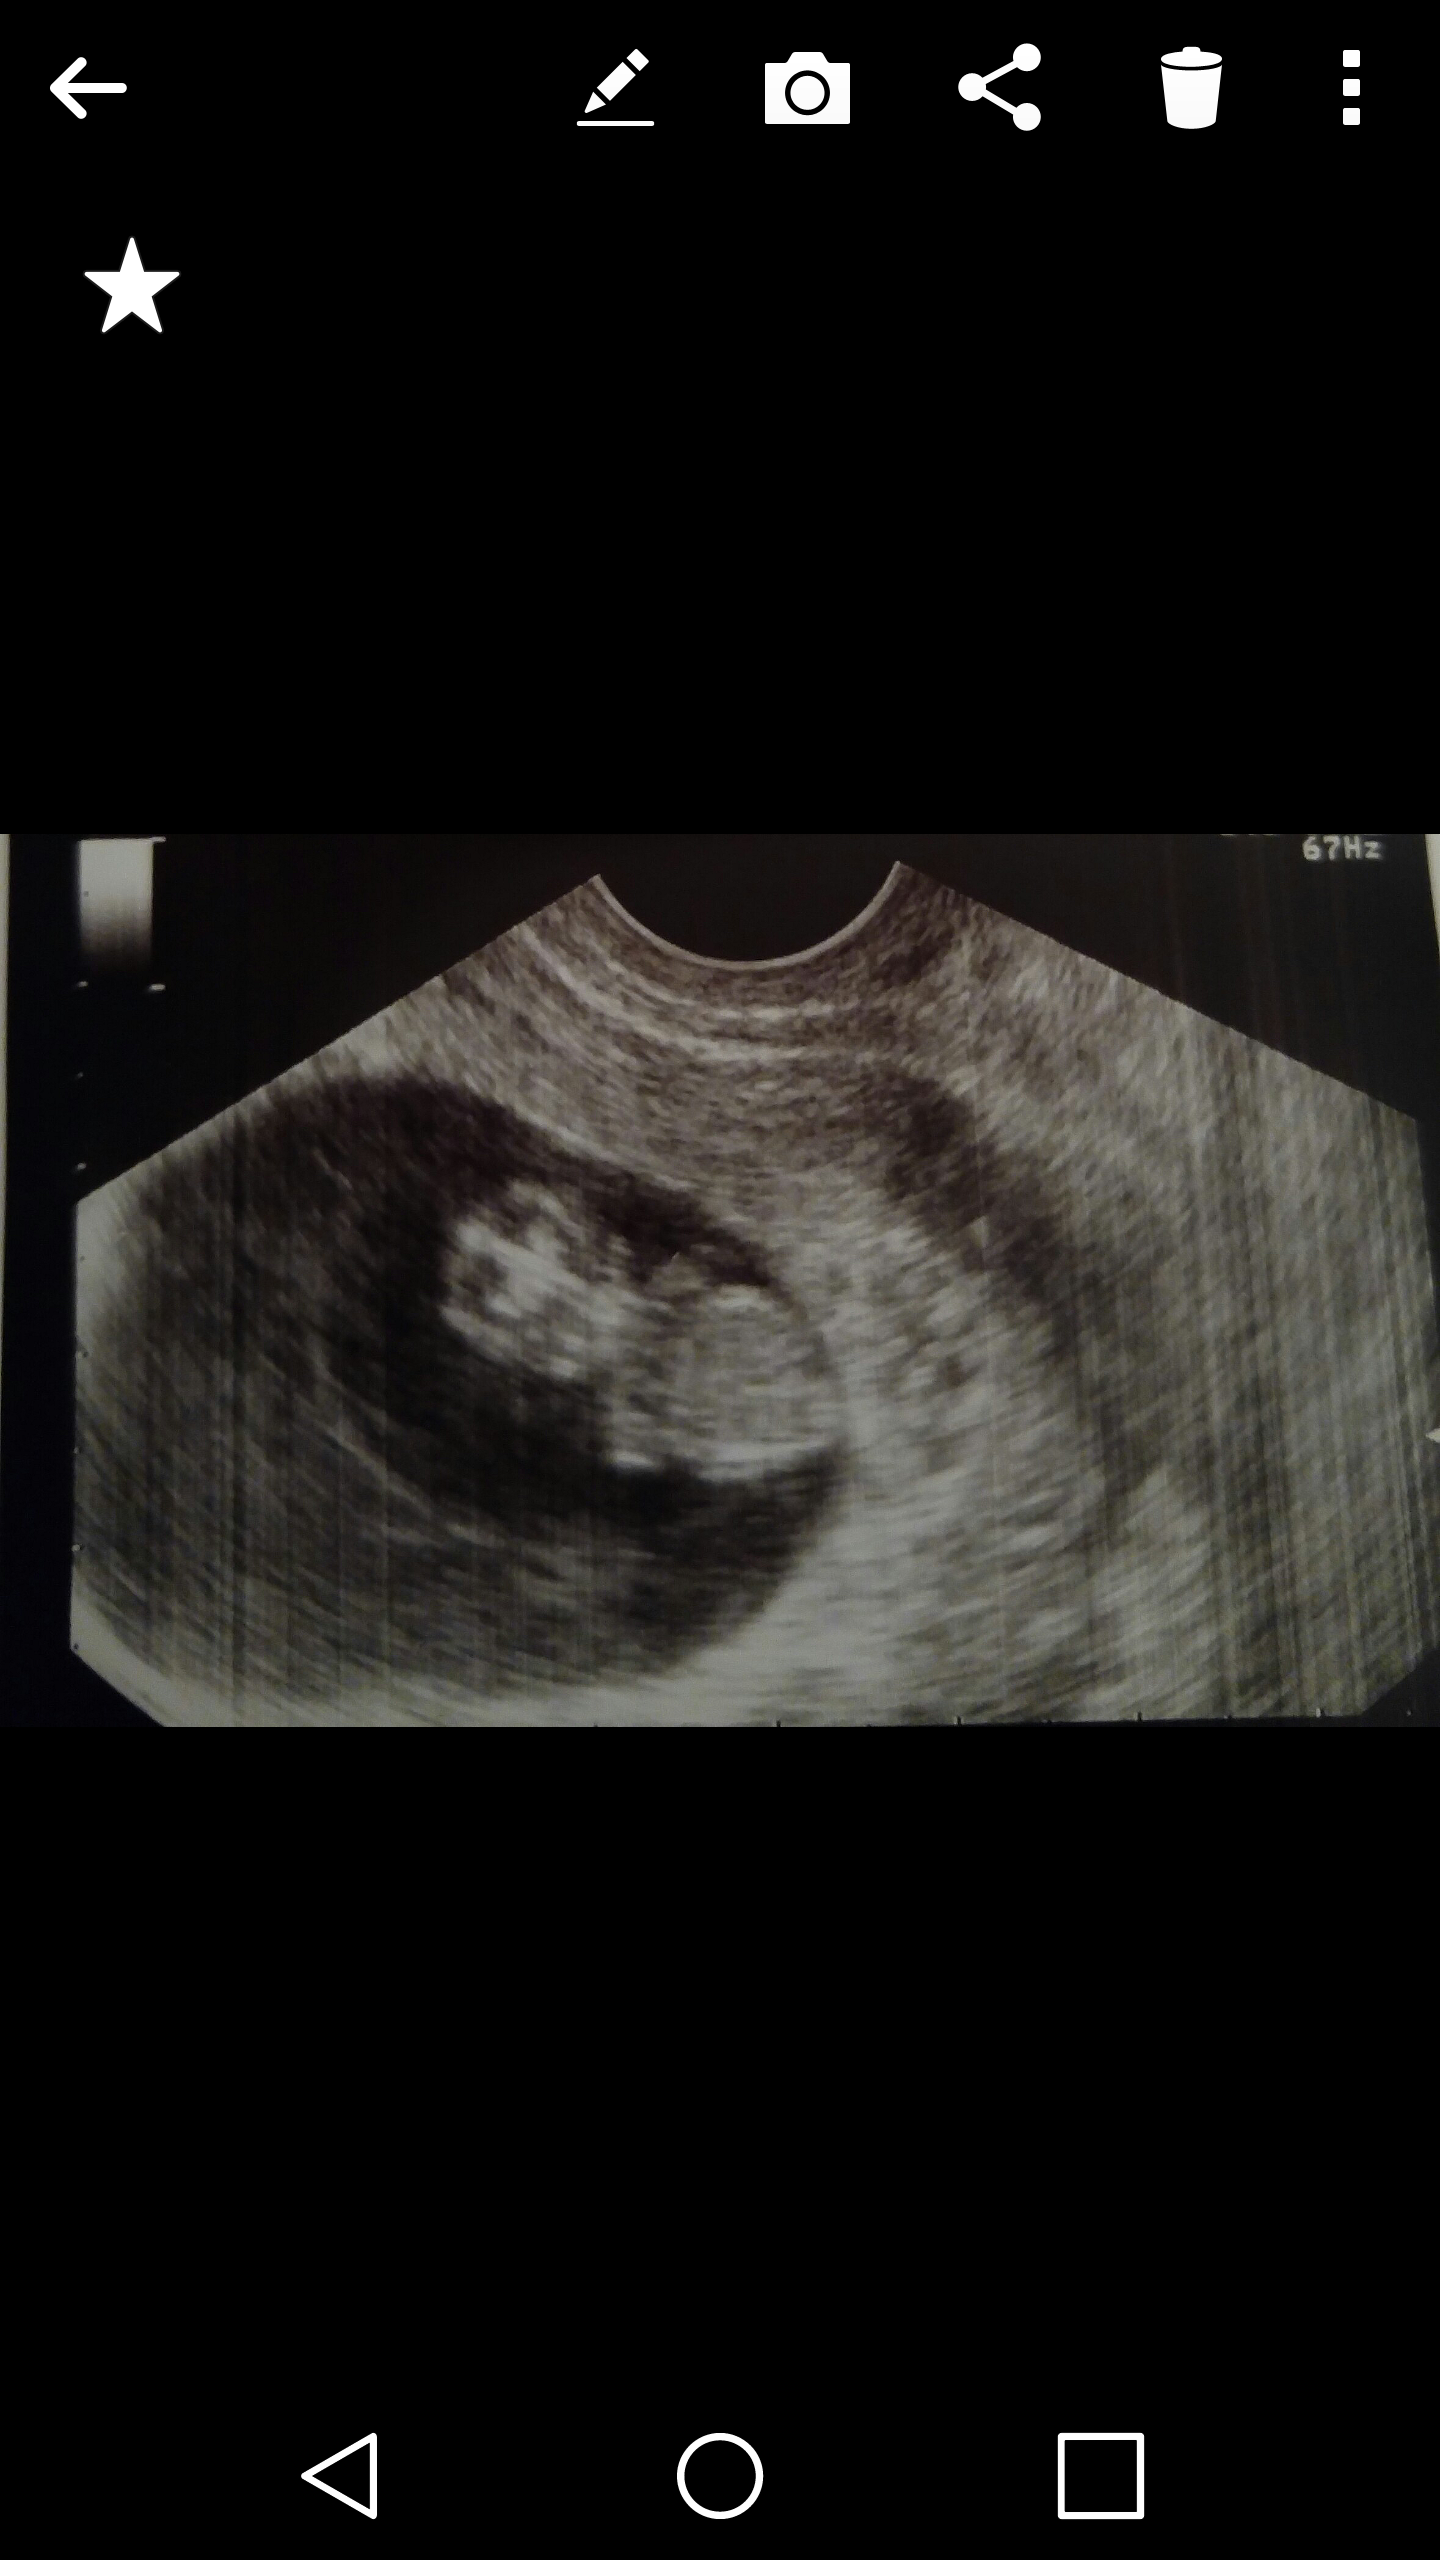

Hello! My name is Diana. 25 years old from Northern California. I've been with my boyfriend 3 and a half years..have known him almost 6. This is our first baby. I am 8w4d pregnant according to my lmp. This is my first baby. I had my first ultrasound which says 8w4d and the gestational age says 9 weeks?my lmp was october 1st through the 6th which means i should have ovulated around the 15th Im a little worried not going to lie...the size is bothering me. It just seems so big for being 9 weeks or less. I did have a transvaginal ultra sound and the doctor did zoom in. Im not positive it that could affect why it looks so big lol im just wondering if the timing is right or could be off or could do it just really already look like its going to be big. Also does anyone understand the ramzi theory? Any guesses?